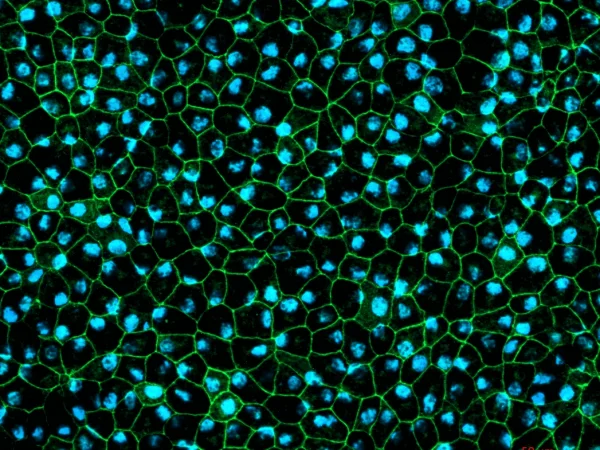

RPE cells displaying cobblestone morphology. Cells were immunolabeled with tight-junction ZO-1 marker (shown in green) and co-stained with nuclei marker, Hoechst (shown in blue). Image Credit: Newcells Biotech

A two-dimensional in vitro model of retinal pigment epithelial cells derived from human induced pluripotent stem cells that replicate the phagocytosis of outer segments of photoreceptors. The RPE cells exhibit the characteristic cobblestone morphology and are pigmented.